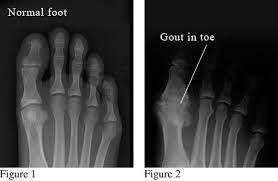

gout

inflammatory arthritis commonly affecting the 1st metatarsophalangeal joint